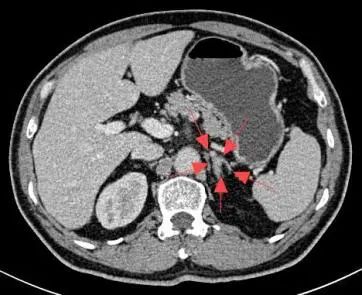

58岁的杨先生患高血压多年,平日里血压控制不佳,近1年来出现血钾减低,间断进行补钾治疗后仍无法将血钾维持在正常范围。于是来到市四医院寻找原因,CT提示左侧肾上腺结节样增生,考虑杨先生存在原发性醛固酮增多症,为了明确双侧肾上腺的优势分泌侧来准确指导外科手术方案。医院介入室团队为患者进行了双侧肾上腺静脉采血术,血检结果提示左侧肾上腺为优势分泌侧。2周后,杨先生在泌尿外科接受了腹腔镜下左侧肾上腺切除术,术后血压恢复正常,无需药物辅助控制。